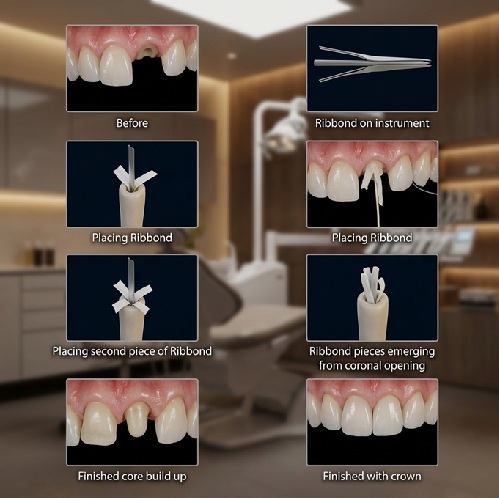

About Ribbond

Ribbond prevents fracture failures in dental composites and acrylics. Ribbond prostheses are strong and maintain their strength with continued use. They are tough and durable. Ribbond’s unique combination of ultra-high strength fibers, enhanced bondability and patented cross-link lock-stitch leno weave makes the strength and fracture toughness of Ribbond reinforced prostheses unsurpassed by other fiber reinforcements.

Versatile:

The unique combination of strength, esthetics and bondability allows Ribbond to be used for many different applications. Ribbond bonds to both composite and acrylic giving you a material with multiple uses.